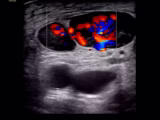

Measurement of systolic blood pressure using POCUS with color Doppler compared to with an intraarterial line

Henry Mayo-Malasky; Daniel Ying; Alekhya Bukkuri; Paul H. Mayo - This study compares the measurement of SBP using point of care ultrasound (POCUS) with color Doppler to the measurement of SBP using an intraarterial catheter